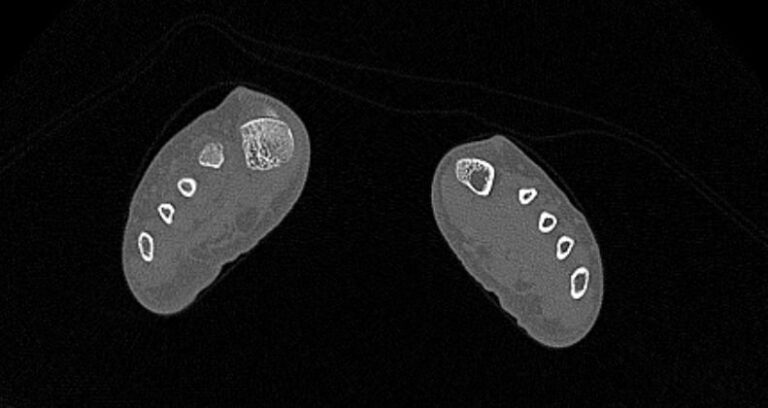

Наиболее точным и информативным методом обследования костных структур стопы является мультиспиральная компьютерная томография. КТ относится к лучевым методам исследования, то есть для визуализации внутренних органов применяется сканирование при помощи рентгеновского излучения, а затем полученные данные проходят цифровую обработку. В результате получается объемная реконструкция исследуемой области, которую можно увеличить, повернуть в разные стороны, оценить расположение анатомических структур и измененных участков в пространстве.

С помощью мультиспиральной КТ проводится точная диагностика травм стопы, позволяющая оценить расположение костных отломков. Метод КТ применяется для визуализации костей стопы при планировании хирургического вмешательства, затем в послеоперационном периоде для оценки правильности репозиции костных отломков и для контроля процессов регенерации кости.

Метод КТ наибольшую информацию дает о состоянии костных структур, так как кости в большей степени поглощают рентгеновские лучи и поэтому хорошо видны на снимках. Для повышения диагностических возможностей метода, в частности, для улучшения визуализации мягких тканей, мышц и связочного аппарата дополнительно используется контрастное усиление.

- переломы и трещины костей с нарушением структур, образованием костных отломков и их смещением;

- полные и неполные вывихи;

- смещения суставных поверхностей;

- деформирующий остеоартроз;

- остеомиелит (секвестрация, патологические переломы);

- асептического некроза костной структуры